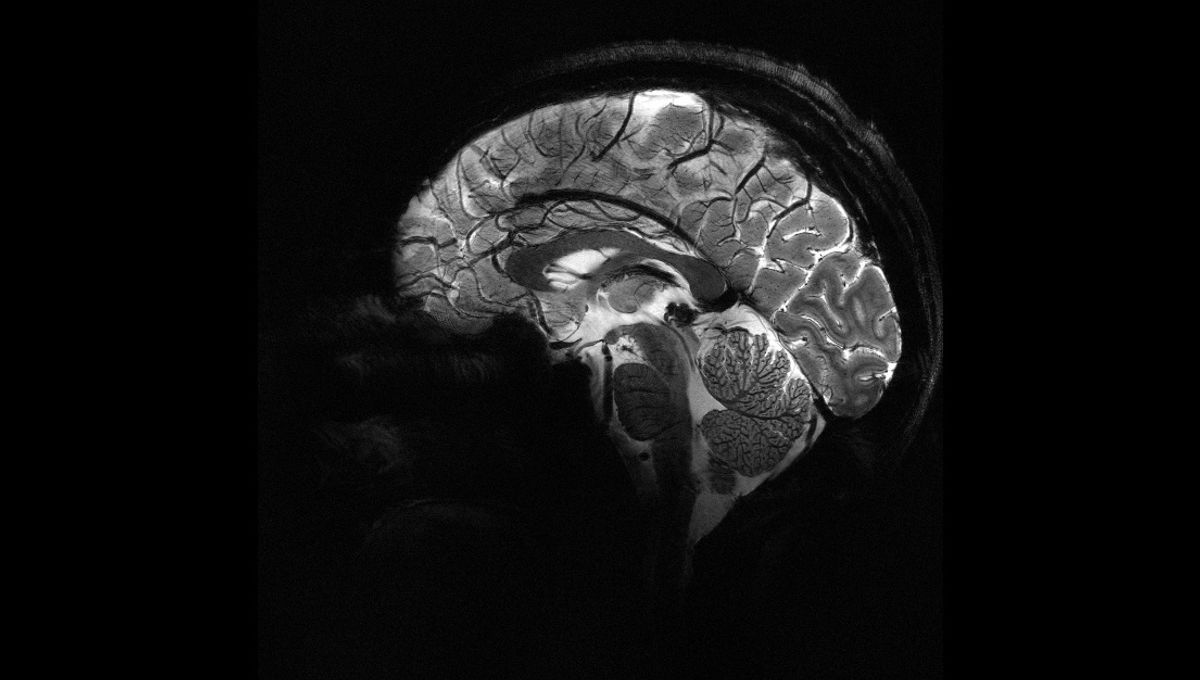

The World’s Most Powerful MRI Machine Just Took Some Stunning Images

View the brain as we’ve never seen it before.